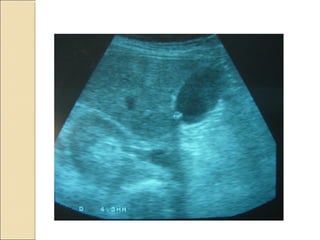

¿Esa imagen negra?¿Esa imagen negra? Corte longitudinal

axial posterior

izquierdo.

Diafragma

Bazo.

Riñón izquierdo.

Imagen

hipoecogénica,

cortical, medial-

inferior anterior.

Dx: QUISTE

CORTICAL

SIMPLE